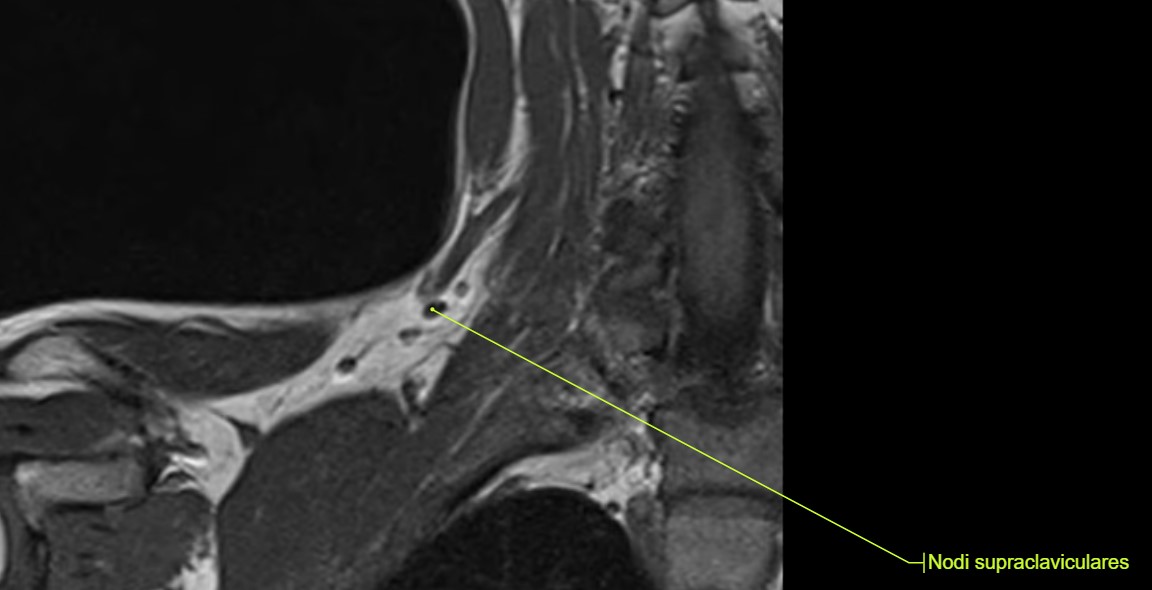

Lymphknoten in der MRT

Lymphknoten sind auf einer MRT (Magnetresonanztomographie) sichtbar, weil sie als Teil des Lymphsystems spezifische Gewebeeigenschaften besitzen, die sich von umliegenden Strukturen unterscheiden. Die MRT nutzt ein starkes Magnetfeld und Radiowellen, um detaillierte Bilder des Körpergewebes zu erzeugen. Dabei macht sich die MRT vor allem Unterschiede in der Wasserstoffkonzentration und den physikalischen Eigenschaften des Gewebes zunutze.

Lymphknoten bestehen aus lymphatischem Gewebe, das eine höhere Dichte an Zellen und Flüssigkeit aufweist als umliegende Strukturen wie Fettgewebe. Diese Unterschiede in der Gewebszusammensetzung führen dazu, dass Lymphknoten je nach verwendeter MRT-Sequenz anders erscheinen als das umliegende Gewebe. Es gibt verschiedene Sequenzen in der MRT, die unterschiedliche Gewebetypen besser hervorheben können.

Zusätzlich können veränderte oder vergrößerte Lymphknoten, die auf Infektionen, Entzündungen oder Tumore hinweisen, noch deutlicher sichtbar sein. In solchen Fällen verändern sich die Eigenschaften der Lymphknoten und sie heben sich noch stärker von gesunden Strukturen ab, was sie auf den MRT-Bildern leichter erkennbar macht.

MRT-Bilder mit Anatomie von Lymphknoten im Becken, Lymphknoten im Halsbereich, sowie einem Lymphknoten im Bereich des Schlüsselbeins: